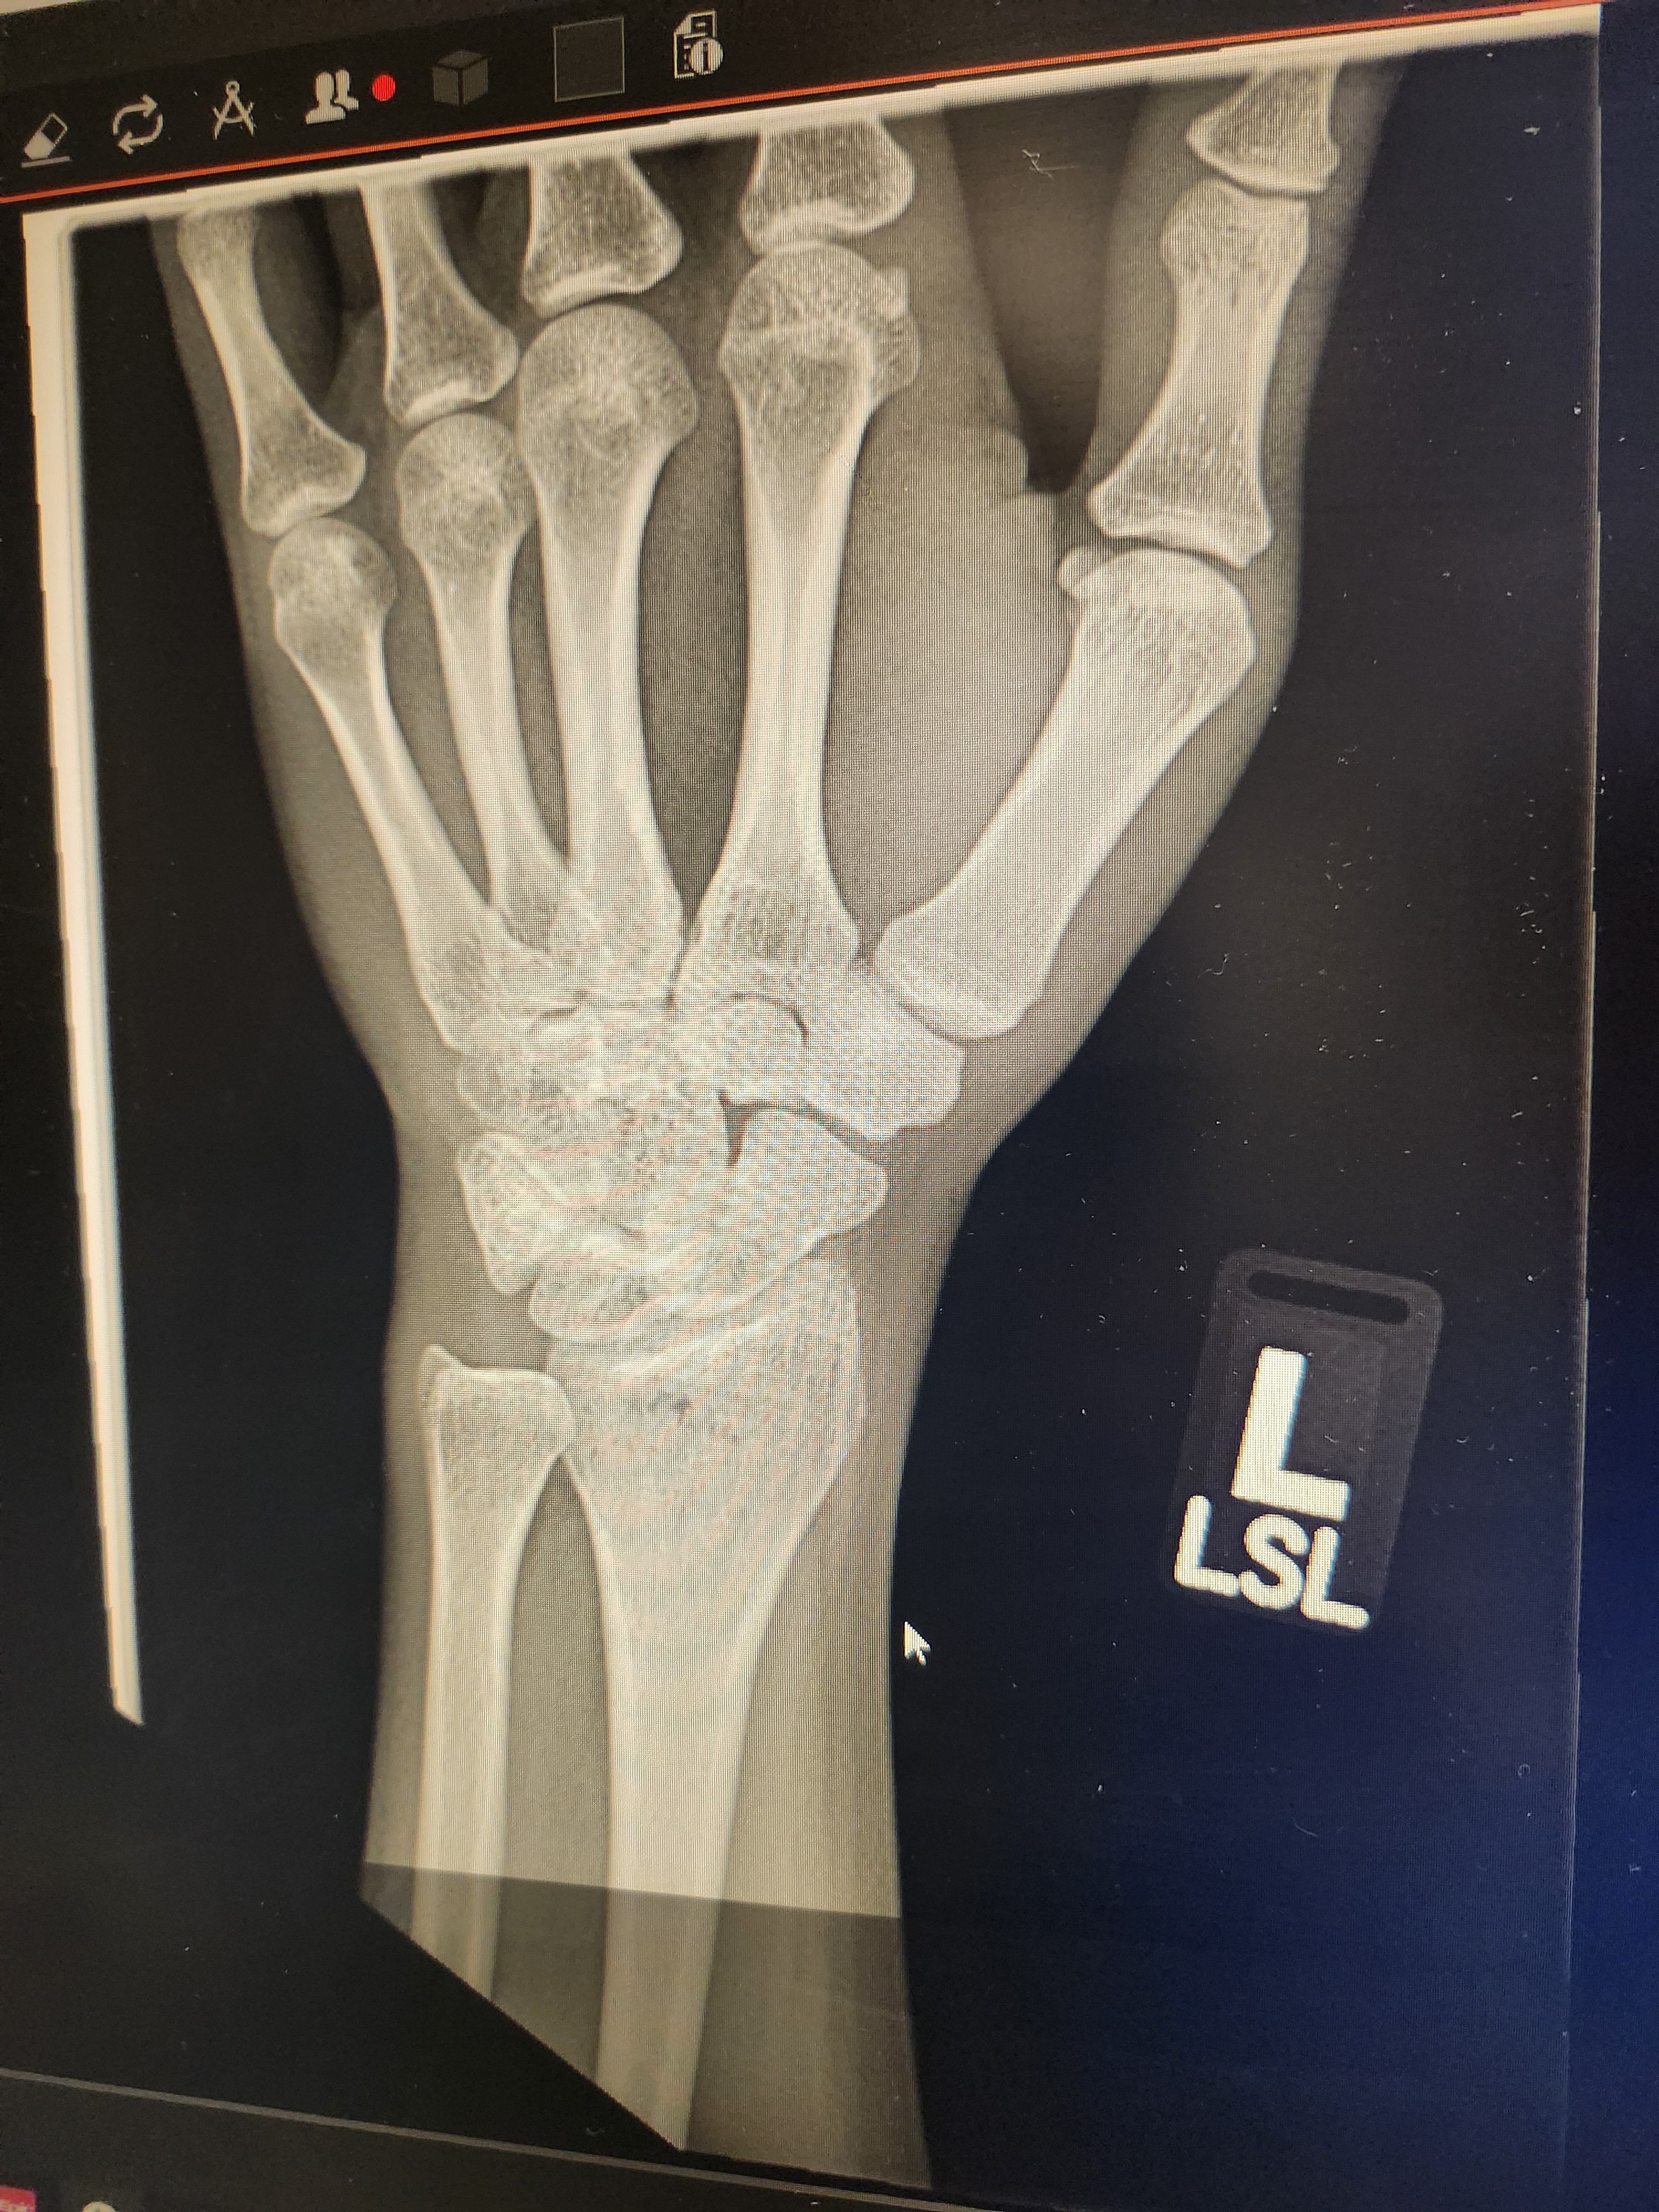

And then "the wind blew me" into a backward roll on concrete and it was a crowded alley so I moved my arm inward to avoid getting crushed by a foot and to not trip anyone. I basically landed wrong and as I pushed myself up on my hand my wrist broke. Oops.